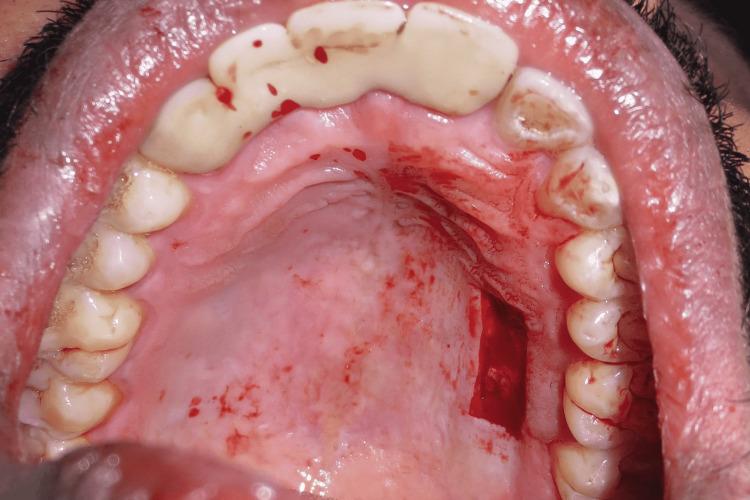

This case report describes Clark's technique of vestibuloplasty to treat shallow vestibule and, in addition, the use of free gingival autograft to augment attached gingiva to treat Miller's recession. Vestibuloplasty is performed to deepen a shallow vestibule. Different vestibuloplasty techniques are used to deepen the shallow vestibule by modifying the soft tissue attachment. A 29-year-old male presented to the Department of Periodontics and Oral Implantology, Regional Dental College, Guwahati, India with the chief complaint of bleeding from the lower anterior along with the gingival recession. Maintenance of regular oral hygiene was an added hindrance. The combined technique of vestibuloplasty and use of free gingival graft was performed to achieve dual benefits of increasing the vestibular depth and attainment of a thick gingival phenotype.

本病例报告描述了克拉克前庭成形术治疗浅前庭的技术,此外,还介绍了使用游离龈自体移植术增加附着龈以治疗米勒氏牙龈退缩的方法。前庭成形术用于加深浅前庭。通过改变软组织附着来加深浅前庭,采用了不同的前庭成形术技术。一名29岁男性因下前牙出血伴牙龈退缩,前往印度古瓦哈蒂地区牙科学院牙周病与口腔种植科就诊。保持规律的口腔卫生是一个额外的障碍。采用前庭成形术和游离龈移植术相结合的技术,以实现增加前庭深度和获得厚龈表型的双重益处。